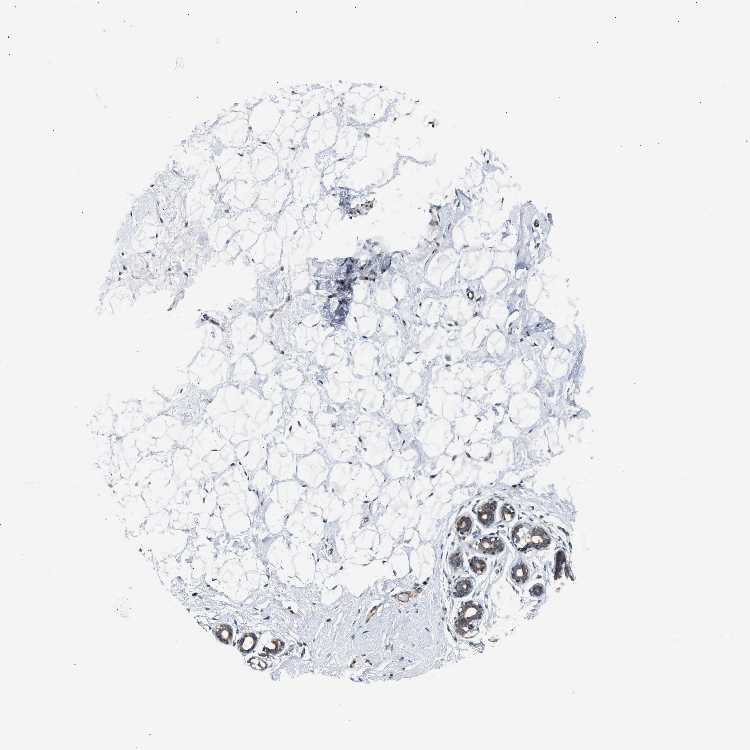

BREAST - Antibody stainingi

Antibody staining in the annotated cell types in the current human tissue is reported as not detected, low, medium, or high, based on conventional immunohistochemistry profiling in selected tissues. This score is based on the combination of the staining intensity and fraction of stained cells.

Each image is clickable and will lead to virtual microscopy that enables deeper exploration of all samples and also displays staining intensity scores, fraction scores and subcellular localization as well as patient and tissue information for each sample.

Antibody HPA018024

Adipocytes Not detected

Glandular cells Medium

Myoepithelial cells Medium